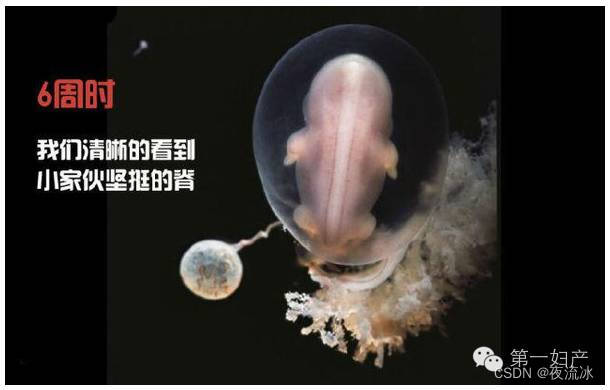

22天后:胚胎尚未发育成熟,但我们可以看到大脑内部了。

24天后:第一批发育的器官,心脏开始跳动